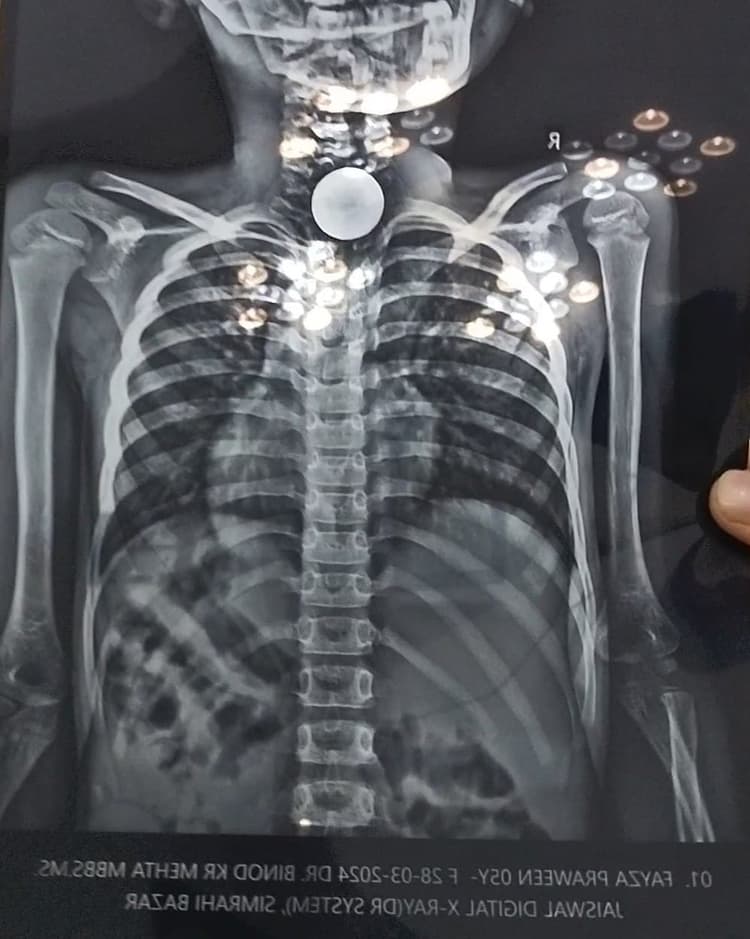

Supaul: राघोपुर (सुपौल). थाना क्षेत्र के सिमराही बाजार में एक नर्सिंग होम में इलाज के क्रम में एक पांच वर्षीय बच्ची की मौत हो गयी. बच्ची को परिजनों ने उसके गले में फंसे सिक्के निकालने के लिए उक्त नर्सिंग होम में भर्ती कराया था. बच्ची की मौत के बाद परिजनों ने चिकित्सक पर लापरवाही का आरोप लगा हंगामा किया. परिजनों ने बताया कि डॉक्टर ने उस बच्ची को बेहोश कर उसका गला काटकर सिक्का निकालने का प्रयास शुरू कर दिया. जिसके बाद मौके पर ही बच्ची की मौत हो गयी. घटना की जानकारी राघोपुर पुलिस को दी. इसके बाद पुलिस ने मौके पर पहुंच डॉक्टर सहित कुछ अन्य कर्मियों को भी अपने कब्जे में लेकर थाना ले आयी. इसके बाद परिजनों ने कई बार प्रभारी चिकित्सा पदाधिकारी डॉ दीप नारायण राम को मोबाइल पर भी फोन किया, लेकिन उन्होंने फोन रिसीव नहीं किया. मृत बच्ची की पहचान वीरपुर थाना क्षेत्र के बेरिया कमाल, लालपुर गोठ निवासी नौशाद आलम की पांच वर्षीय पुत्री फैजा प्रवीण के रूप में हुई है.

मृत बच्ची के परिजनों ने बताया कि बच्ची ने करीब तीन-चार दिन पूर्व ही सिक्का निगल लिया था. इसके बावजूद वह ठीक ठाक थी और अच्छे से खाना-पीना भी खा रही थी. बताया कि गुरुवार की संध्या उनलोगों ने बच्ची को सिमराही के करजाईन रोड स्थित साईं नर्सिंग होम में इलाज करवाने के लिए लाया. जहां अस्पताल के संचालक ने बताया कि इसका ऑपरेशन करना पड़ेगा और इसमें दस हजार रुपये खर्च आयेगा. इसके बाद परिजनों ने अस्पताल संचालक के पास नौ हजार रुपये जमा करवा दिया. इसके बाद अस्पताल संचालक ने सम्राट नाक कान गला हॉस्पिटल के डॉक्टर विनोद कुमार मेहता को बुलाया. इसके बाद डॉक्टर ने बच्ची को एनेथेसिया डालकर बेहोश कर दिया और गले पर जैसे ही चीरा लगाया, बच्ची की मौत हो गयी.